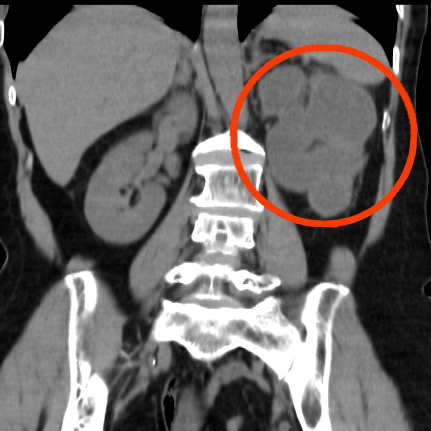

泌尿外科主治医师邱焕双结合病史,为她安排了CT等检查,发现情况远比蔡阿姨预想的棘手——左肾重度积水、急性肾盂肾炎。

“患者是结石梗阻引发了肾积水,已经是无功能,再拖下去还可能面临脓毒血症、尿毒症等风险,危及性命,需要尽快切除肾脏。”邱焕双解释,从检查来看,患者结石应该已经多年,但可惜没有及时发现治疗,才引发了如此严重的并发症。

术中,在腹腔镜下可见,肾只有一层皮囊,肾内大量脓性分泌物,正是肾内积脓导致反复发热。